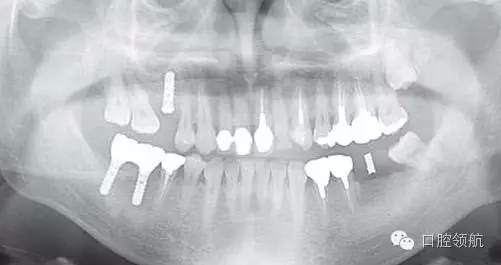

對患者進行詳細說明后,拔除后等待骨愈合6個月,再度植入手術。第二次植入時,注意了沖水充分,根據(jù)骨的狀態(tài),在缺損部中央植入。植入后2個月,按常規(guī)戴入上部結構,約6個月后,曲面斷層影像和口內(nèi)均未見異常,愈合良好(圖9)。

圖9 再植入后6個月的曲面斷層影像。